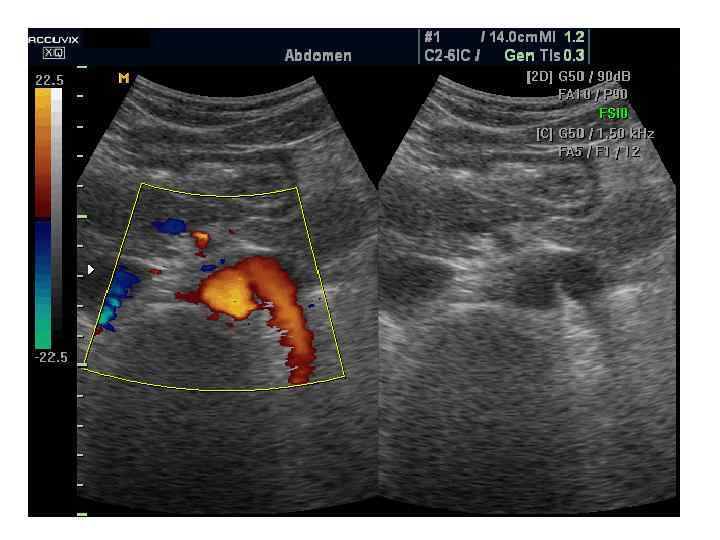

УЗИ сосудов почек

Цветовой допплер (Color Doppler) Кровоток • к датчику принято картировать красным цветом, • от датчика - синим цветом. • Турбулентный кровоток картируется сине-зелено-желтым цветом.

Энергетический допплер (Power Doppler). • Применяется для регистрации низкоскоростного кровотока. • При использовании энергетического допплера теряется направление кровотока. • В настоящее время энергетический допплер используют в сочетании с контрастными веществами (левовист и др. ).